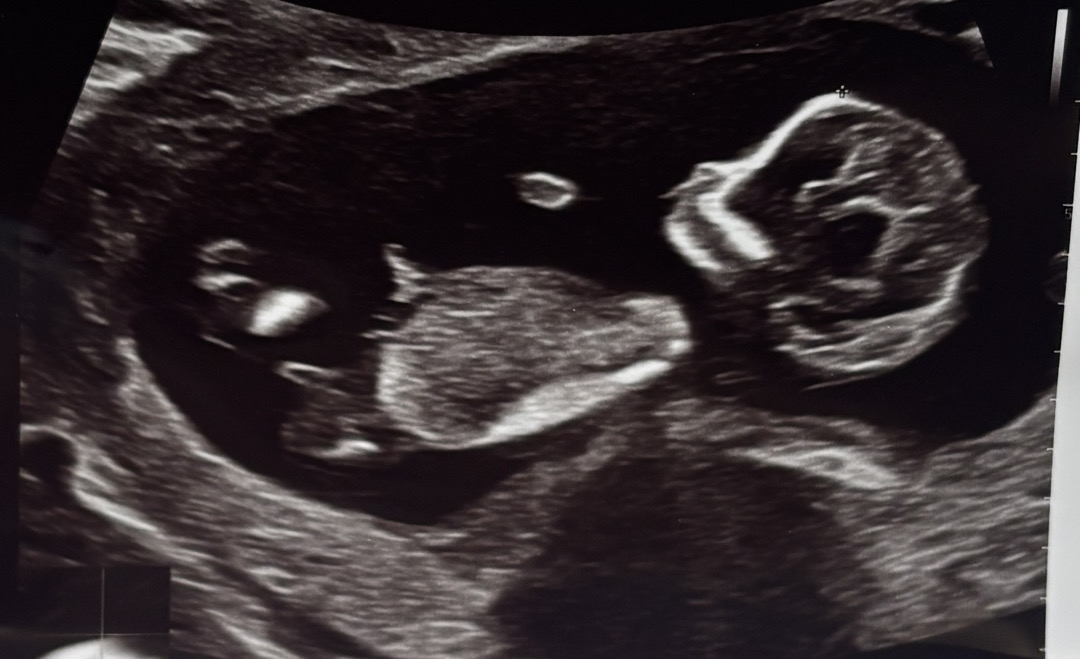

12주3일차인데 이르지만 각도법 고수님 계신가요..?

이 사진으로도 가능할까요?!

방광이 보여야 판단하기 좋을거같아요